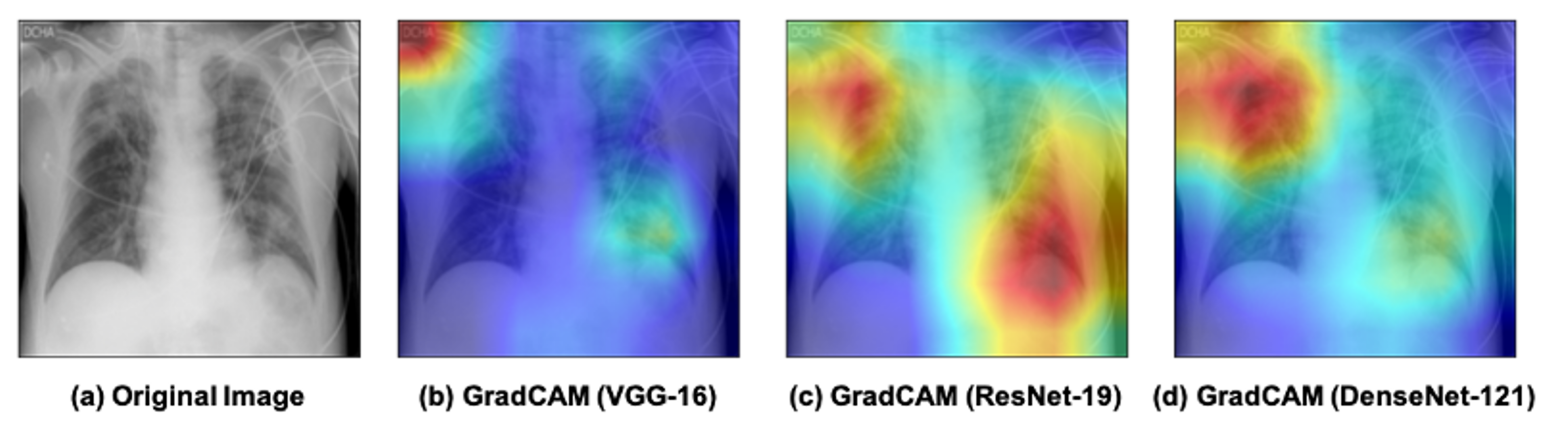

Gradient-weighted Class Activation Mapping (Grad-CAM) [57] proposed by Selvaraju et al. uses the gradients flowing down to the last convolutional layer to multiply CAM from a forward pass. The resolution is enhanced by multiplying Grad-CAM with guided-backpropagated gradients. Class-specific queries and counterfactual explanations supported by Grad-CAM enable the visualization of portions of a picture that have a detrimental impact on model output, as shown in Fig. 9. Grad-CAM++ [58] replaces the globally averaged gradients in Grad-CAM with a weighted average of the pixel-wise gradients since the weights of pixels contribute to the final prediction, which leads to better visual explanations of CNN model predictions. It addresses the shortcomings of Grad-CAM, especially multiple occurrences of a class in an image and poor object localization.

Refer to caption

Figure 9: Comparison of different network visualization with GradCAM. The heatmaps are overlapped on the original image, where the red color highlights the activation region associated with the predicted class (COVID-19). (a) original image (b) GradCAM with VGG-16 (c) GradCAM with ResNet-18 (d) GradCAM with DenseNet 121.